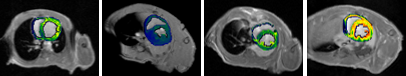

7.0T MRI结合心肌ECV定量技术对于临床无创评估心脏疾病具有重要意义。通过多参数成像技术(如钆对比剂延迟增强),测量心肌细胞外容积 (ECV)的变化(图2),能够更敏感地捕捉到轻度心肌炎症、药物导致的心肌水肿等早期病变,为疾病的早期干预提供依据。

图2 小鼠肥厚型心肌病ECV量化分析